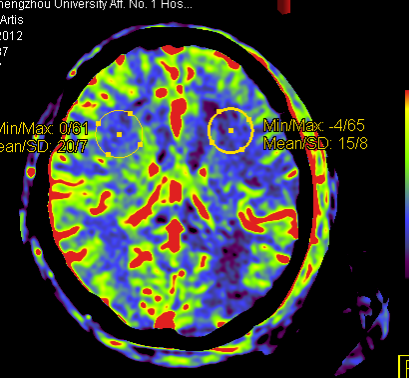

神经及灌注成像PBV显示组织血容量灌注信息的功能学影像,并根据彩色 编码进行量化,病人无需转运到CT室就能得到病灶完整的灌注信息。

彩色血流编码iFlow基于DSA造影序列一键式生成彩色编码图像,直观且量化的显示血流动力学信息,如造影剂达峰时间等。通过血流达峰时间定量分析对术前术后疗效进行评估。